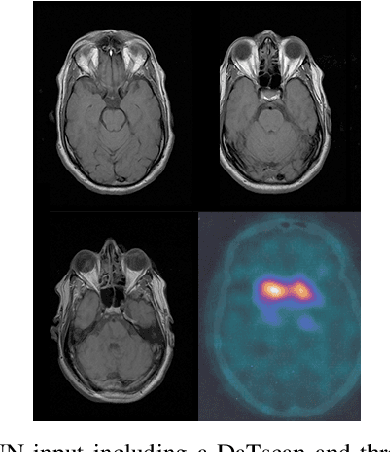

Abstract:The paper presents a novel approach, based on deep learning, for diagnosis of Parkinson's disease through medical imaging. The approach includes analysis and use of the knowledge extracted by Deep Convolutional and Recurrent Neural Networks (DNNs) when trained with medical images, such as Magnetic Resonance Images and DaTscans. Internal representations of the trained DNNs constitute the extracted knowledge which is used in a transfer learning and domain adaptation manner, so as to create a unified framework for prediction of Parkinson's across different medical environments. A large experimental study is presented illustrating the ability of the proposed approach to effectively predict Parkinson's, using different medical image sets from real environments.